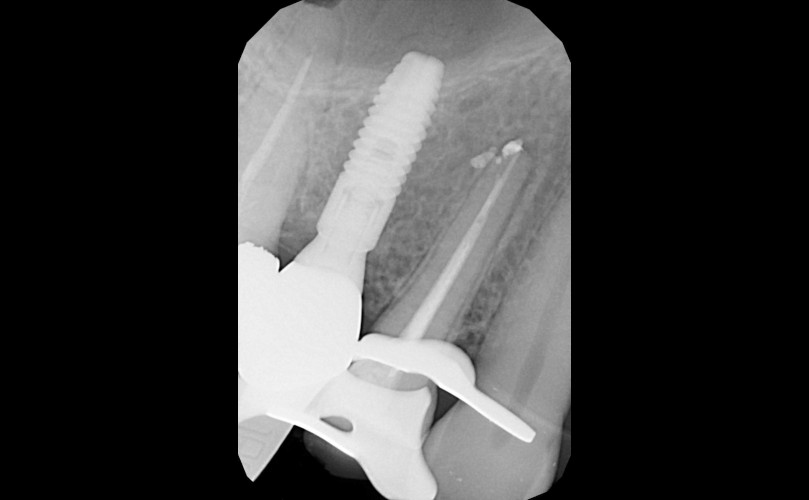

Para su diagnóstico, en nuestra Clínica Dental de Santa Cruz de Tenerife, disponemos de tecnología radiográfica digital de última generación que permite un diagnóstico preciso, de manera inmediata y con una radiación bajísima en comparación con los antiguos aparatos de radiografía dental, así como una formación especialista en endodoncia. Es la única manera de conservar nuestro diente en la boca.

• Lo primero siempre es diagnosticar correctamente, realizando un correcto estudio radiográfico y de pruebas de sensibilidad y de presión procedemos con la endodoncia.

• Instrumentemos la, o las raíces hasta su final, mediante el uso de limas de aleaciones muy flexibles que nos permiten trabajar anatomías muy complejas, líquidos desinfectantes, y todo controlado por instrumentos de última generación y radiografías.

• Posteriormente a la completa desinfección, rellenamos esas raíces con cementos y resinas totalmente biocompatibles e inocuas mediante técnicas de compactación por calor, que nos aseguran un sellado tridimensional.

Cuando una endodoncia previamente realizada no se ha conseguido desinfectar completamente las raíces, o no se ha conseguido un sellado correcto de estas, pueden provocar dolor, inflamación y lesiones en el hueso.

Cuando esto ocurre, se necesita retratar o reendodonciar el diente. Este tratamiento es de muy alta dificultad, ya que no solo se lucha contra la anatomía compleja del diente, sino que también contra los problemas causados por el tratamiento previo, como infecciones, alteraciones de la anatomía, materiales de difícil eliminación, limas rotas…